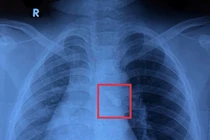

Trường hợp thứ hai là bệnh nhân H.X.T, 74 tuổi, xã Vũ Thư (Hưng Yên). Sau khi hóc xương khoảng 2 giờ, bệnh nhân đến viện khám với biểu hiện đau nhiều vùng cổ, vị trí ngang bờ trên xương ức. Khám lâm sàng, nội soi họng, hạ họng, thanh quản không phát hiện dị vật. Chụp X- quang cũng không thấy hình ảnh dị vật cản quang. Khi tiến hành nội soi thực quản, bác sĩ phát hiện xương cá ở đoạn 1/3 trên và gắp thành công. Sau can thiệp, bệnh nhân hết đau, được kê đơn thuốc và hướng dẫn theo dõi sức khoẻ tại nhà.